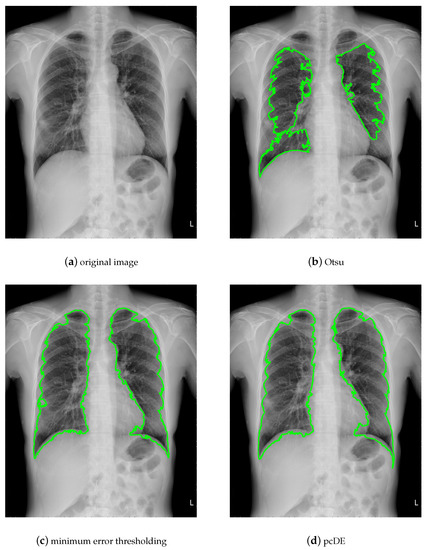

5. Case of Study: Parallel Compact Differential Evolution for Image Segmentation

- Image preprocessing. Enhance the contrast of the image to achieve better segmentation.

- Calculate the optimal threshold for image segmentation through different methods to get the binarized image.

- Use morphological methods to process images to extract targets.

- Mark target contour.

- : Represent the result of ground truth segmentation (Figure 13).

- : Represent the result of algorithm segmentation.

| Segmentation Method | Original Image | Noisy Image |

|---|---|---|

| Otsu | 0.9210 | 0.9531 |

| minimum error thresholding | 0.9732 | 0.9093 |

| pcDE | 0.9738 | 0.9684 |